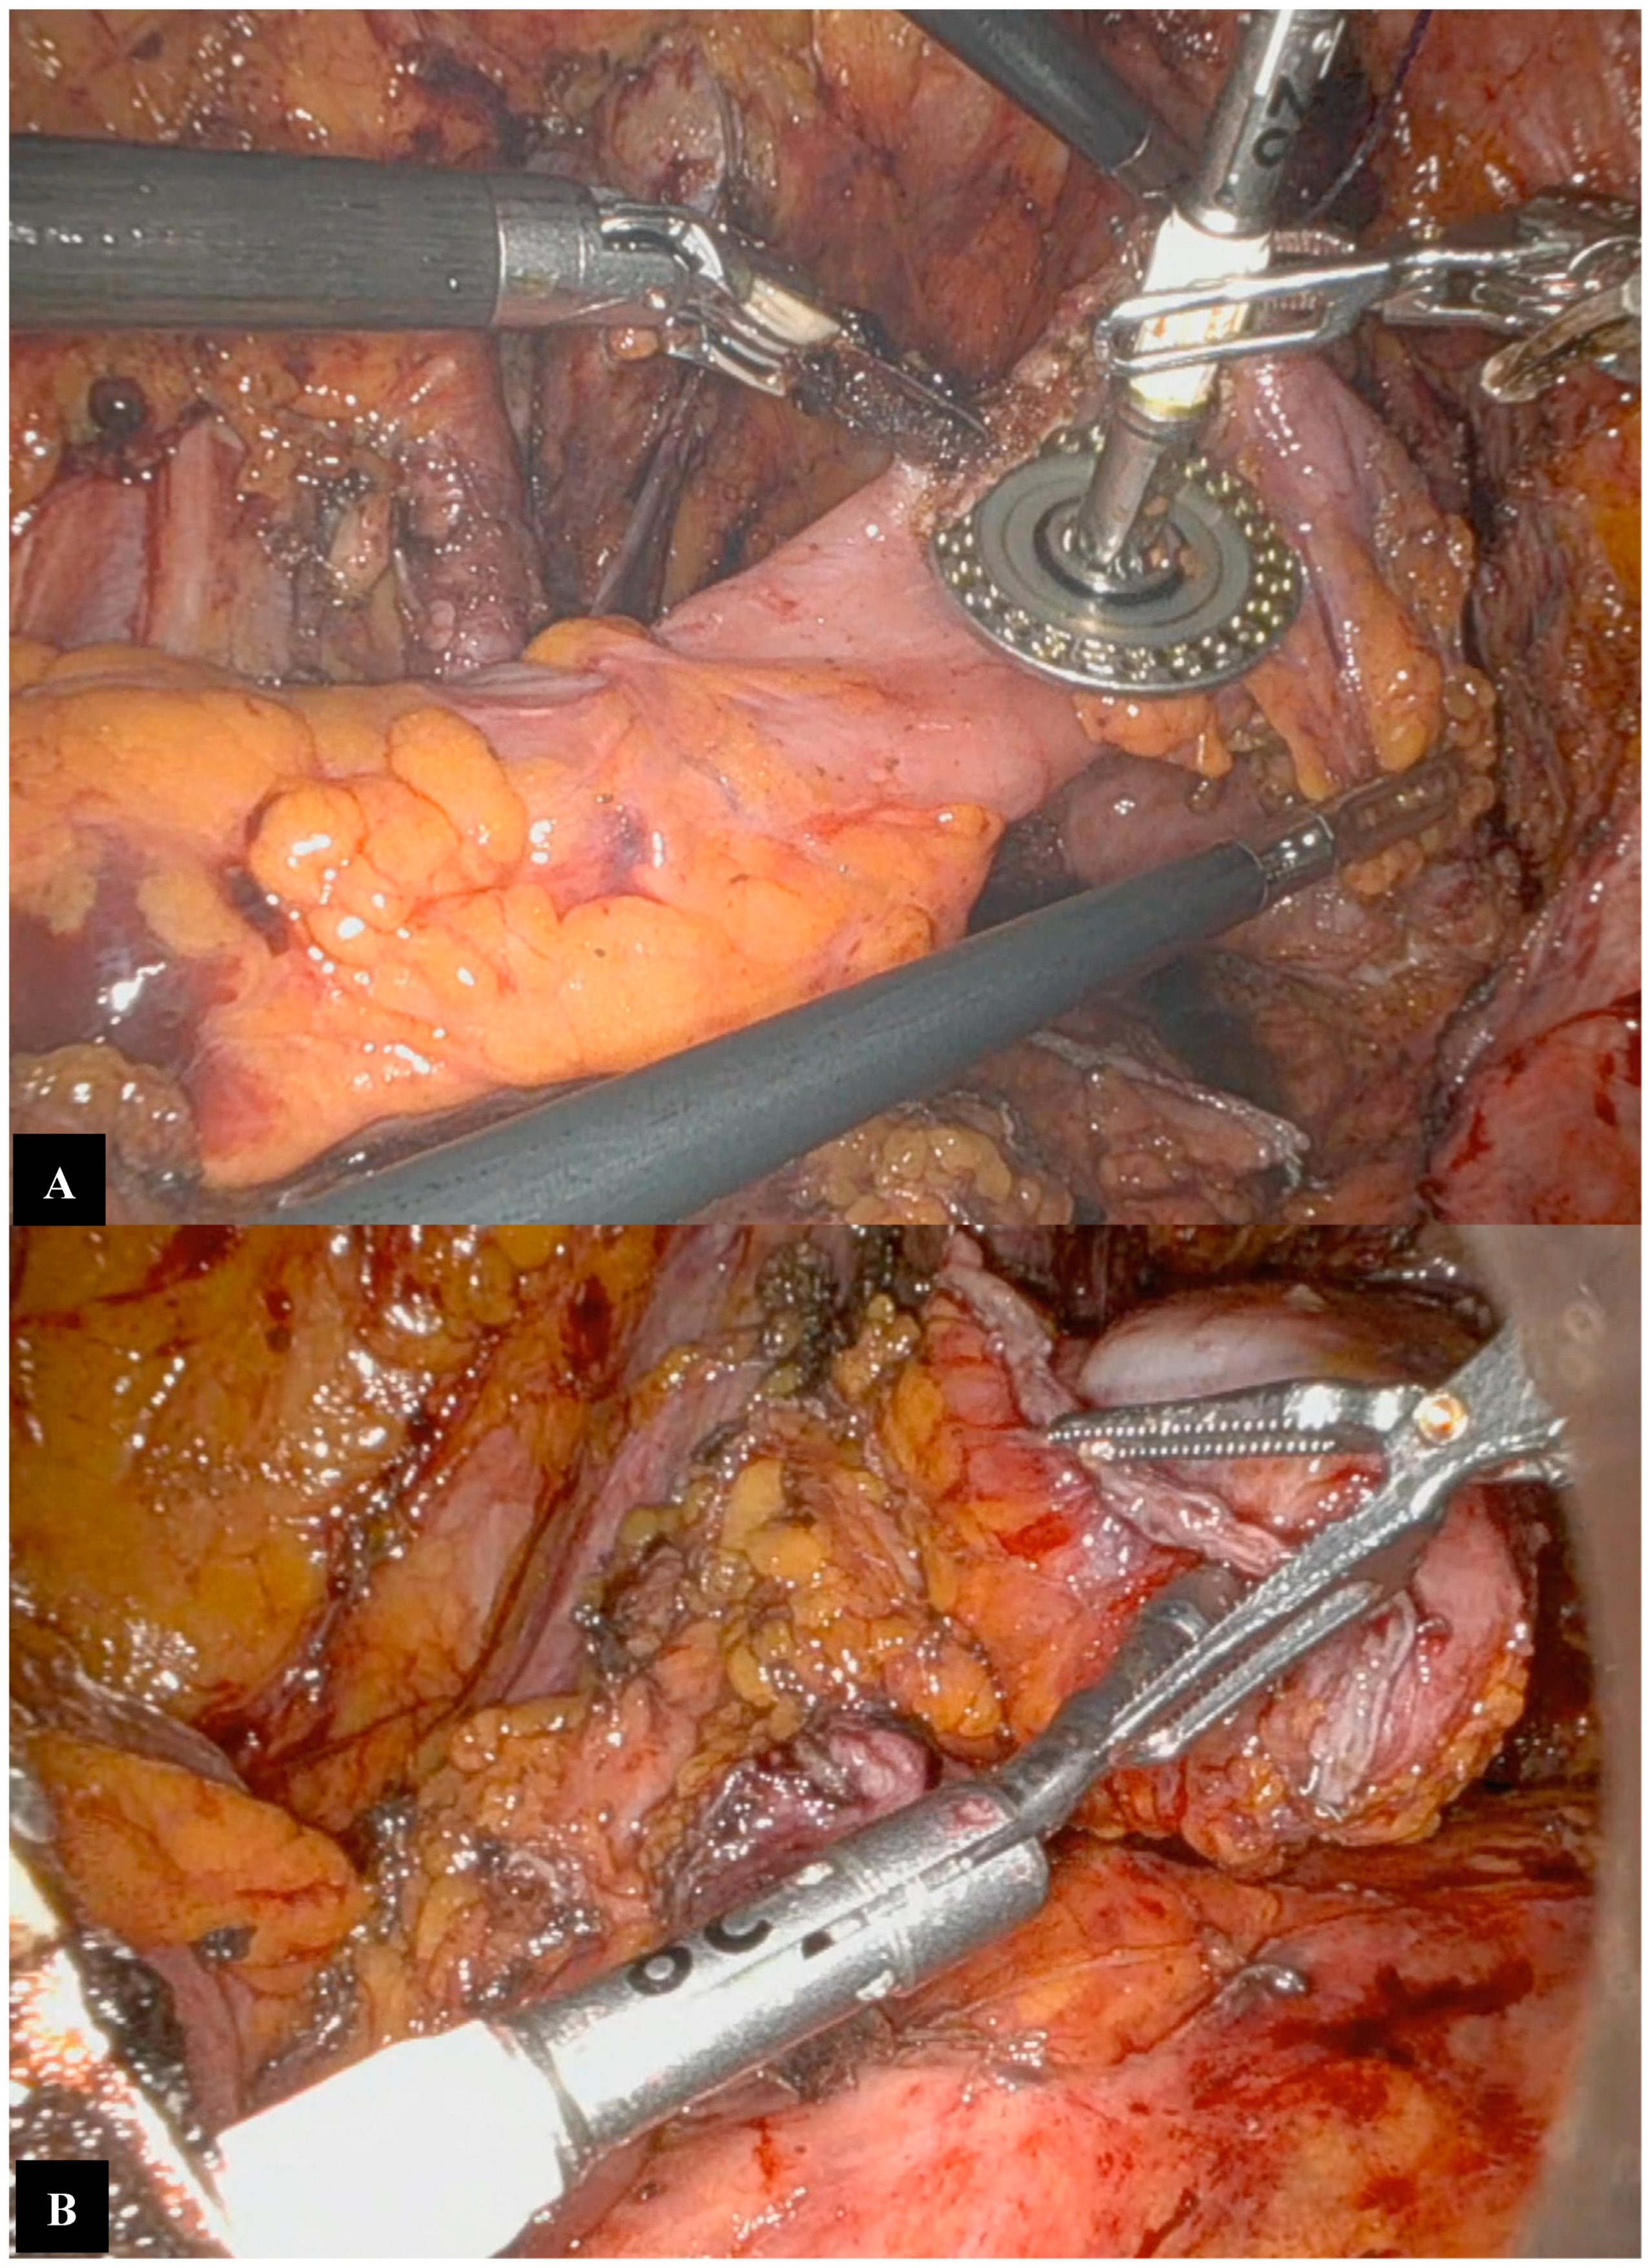

Operative Technique